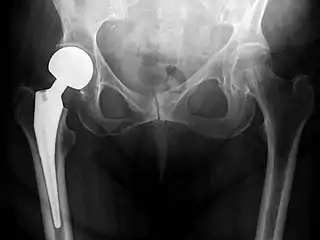

An X-ray showing a left hip (right of image) that has been replaced, with the ball of this ball-and-socket joint replaced by a metal head that is set in the femur and the socket replaced by a cup